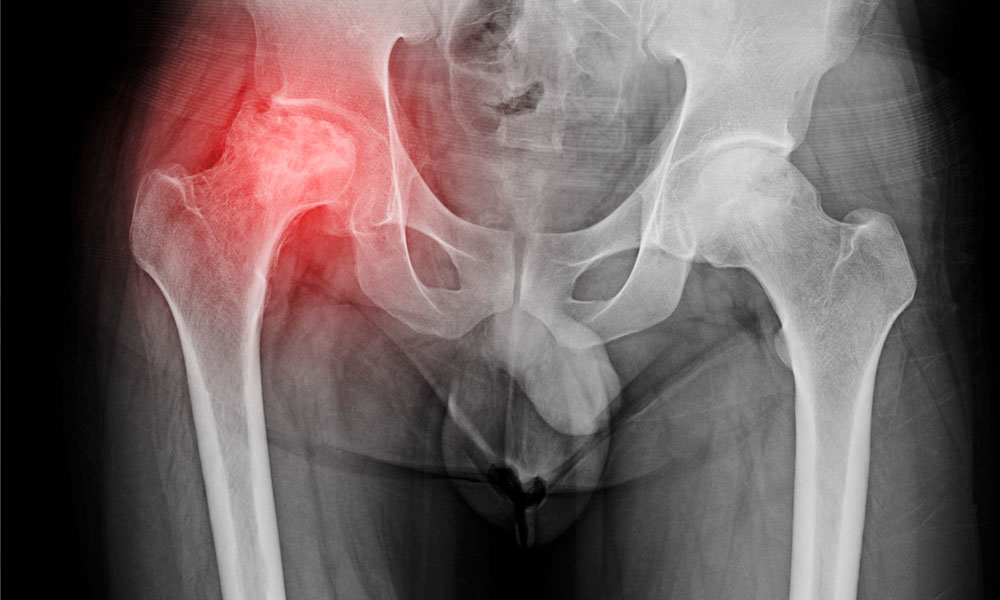

Este estudio retrospectivo evaluó la asociación entre el número de sesiones de inyección de ozono médico intraarticular y los resultados clínicos en pacientes con osteoartritis de cadera (OA). .

Se analizaron los datos de 54 pacientes (65 caderas) con OA de cadera de grado 1-2 de Tönnis tratados en una clínica terciaria de algología entre 2022 y 2024. Los pacientes se clasificaron en tres grupos según el número de sesiones de ozono médico recibidas (1, 2 o 3). El dolor y el estado funcional se evaluaron utilizando la Escala Visual Analógica (EVA) y el índice de Osteoartritis de las Universidades de Western Ontario y McMaster (WOMAC) al inicio y a las 4, 12 y 24 semanas después del procedimiento.